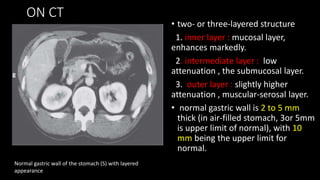

• two- or three-layered structure

1. inner layer : mucosal layer,

enhances markedly.

2. intermediate layer : low

attenuation , the submucosal layer.

3. outer layer : slightly higher

attenuation , muscular-serosal layer.

• normal gastric wall is 2 to 5 mm

thick (in air-filled stomach, 3or 5mm

is upper limit of normal), with 10

mm being the upper limit for

normal.

Normal gastric wall of the stomach (S) with layered

appearance